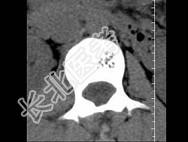

- 单项选择题根据所提供的图像,最可能的诊断 ( )

A、骨结核

B、多发性骨转移

C、骨血管瘤

D、退行性变

E、骨质疏松